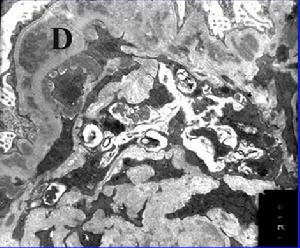

光鏡下部分腎小球,特別是位於皮髓質交界處的腎小球呈節段性玻璃樣硬化,即PAS陽性物質沉積。有時可見硬化區周圍上皮細胞增生並與腎小囊粘連。

1.腎活檢光鏡檢查典型的FSGS病變特徵為腎小球局灶性節段性損害,病變累及少數腎小球及腎小球部分節段的玻璃樣硬化。病變常從皮質深層或近髓部位腎小球開始,逐漸擴展至腎皮質。病變腎小球呈節段性硬化,未受累的腎小球正常或系膜基質增加。透明樣物質沉積於受損毛細血管襻的內皮細胞下,硬化區偶有泡沫細胞形成,常見局限性上皮細胞增生。早期病變可能僅有局部上皮細胞與基膜脫離,上皮細胞腫脹,空泡變性、胞質呈嗜鹼性。硬化毛細血管襻可與包曼囊壁粘連。每個腎小球節段性損害的範圍不同,疾病進展時可造成全球硬化。病變充分發展的病例,易誤認為“非特異性”慢性硬化性腎小球腎炎,可通過免疫螢光檢查鑑別診斷。腎小管損害常表現為基膜局灶性增厚及萎縮。如局灶性腎小管損害與輕微腎小球改變並存,應高度懷疑FSGS。腎組織中局灶性、全球性腎小球硬化的出現常為晚期FSGS的表現,同時伴發重度腎小管間質病變,在兒童患者中高達30%。成人典型的激素敏感性微小病變,可見到少數球性硬化的腎小球,應與FSGS相區別。除原發性FSGS以外,許多疾病的腎組織可見到類似FSGS的改變。FSGS亦可與原發性腎小球疾病相重疊。